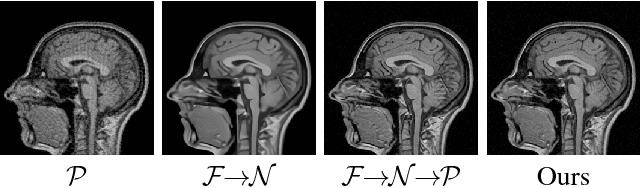

Abstract:Conventional deformable registration methods aim at solving a specifically designed optimization model on image pairs and offer a rigorous theoretical treatment. However, their computational costs are exceptionally high. In contrast, recent learning-based approaches can provide fast deformation estimation. These heuristic network architectures are fully data-driven and thus lack explicitly domain knowledge or geometric constraints, such as topology-preserving, which is indispensable to generate plausible deformations. To integrate the advantages and avoid the limitations of these two categories of approaches, we design a new learning-based framework to optimize a diffeomorphic model via multi-scale propagations. Specifically, we first introduce a generic optimization model to formulate diffeomorphic registration with both velocity and deformation fields. Then we propose a schematic optimization scheme with a nested splitting technique. Finally, a series of learnable architectures are utilized to obtain the final propagative updating in the coarse-to-fine feature spaces. We conduct two groups of image registration experiments on 3D adult and child brain MR volume datasets including image-to-atlas and image-to-image registrations. Extensive results demonstrate that the proposed method achieves state-of-the-art performance with diffeomorphic guarantee and extreme efficiency.

Abstract:Compressed Sensing Magnetic Resonance Imaging (CS-MRI) significantly accelerates MR data acquisition at a sampling rate much lower than the Nyquist criterion. A major challenge for CS-MRI lies in solving the severely ill-posed inverse problem to reconstruct aliasing-free MR images from the sparse k-space data. Conventional methods typically optimize an energy function, producing reconstruction of high quality, but their iterative numerical solvers unavoidably bring extremely slow processing. Recent data-driven techniques are able to provide fast restoration by either learning direct prediction to final reconstruction or plugging learned modules into the energy optimizer. Nevertheless, these data-driven predictors cannot guarantee the reconstruction following constraints underlying the regularizers of conventional methods so that the reliability of their reconstruction results are questionable. In this paper, we propose a converged deep framework assembling principled modules for CS-MRI that fuses learning strategy with the iterative solver of a conventional reconstruction energy. This framework embeds an optimal condition checking mechanism, fostering \emph{efficient} and \emph{reliable} reconstruction. We also apply the framework to two practical tasks, \emph{i.e.}, parallel imaging and reconstruction with Rician noise. Extensive experiments on both benchmark and manufacturer-testing images demonstrate that the proposed method reliably converges to the optimal solution more efficiently and accurately than the state-of-the-art in various scenarios.

Abstract:Magnetic Resonance Imaging (MRI) is one of the most dynamic and safe imaging techniques available for clinical applications. However, the rather slow speed of MRI acquisitions limits the patient throughput and potential indi cations. Compressive Sensing (CS) has proven to be an efficient technique for accelerating MRI acquisition. The most widely used CS-MRI model, founded on the premise of reconstructing an image from an incompletely filled k-space, leads to an ill-posed inverse problem. In the past years, lots of efforts have been made to efficiently optimize the CS-MRI model. Inspired by deep learning techniques, some preliminary works have tried to incorporate deep architectures into CS-MRI process. Unfortunately, the convergence issues (due to the experience-based networks) and the robustness (i.e., lack real-world noise modeling) of these deeply trained optimization methods are still missing. In this work, we develop a new paradigm to integrate designed numerical solvers and the data-driven architectures for CS-MRI. By introducing an optimal condition checking mechanism, we can successfully prove the convergence of our established deep CS-MRI optimization scheme. Furthermore, we explicitly formulate the Rician noise distributions within our framework and obtain an extended CS-MRI network to handle the real-world nosies in the MRI process. Extensive experimental results verify that the proposed paradigm outperforms the existing state-of-the-art techniques both in reconstruction accuracy and efficiency as well as robustness to noises in real scene.